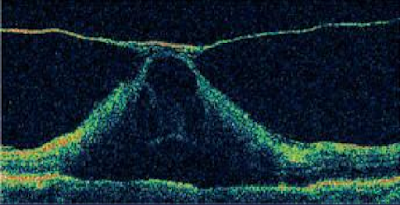

| Fig. 32 Estroma foveal ausente por presencia de agujero macular grado 4 |